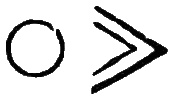

Symp. Each febrile paroxysm is of three periods or stages—the cold, the hot, and the sweating stage, and these occur in regular succession. The cold stage commences with great languor and aversion to motion; a sense of coldness down the back soon follows; then the extremities become cold, the fingers shrunken, and the nails blue; the skin assumes that peculiar condition which is commonly known as ‘goose-skin,’ the patient shivers, his teeth chatter, and he is glad to draw close to the fire or envelop himself in blankets. After this state of things has continued for a greater or less time, the heat of the surface begins to return, the patient has flushings and becomes warmer and warmer, and ultimately the whole surface is of a dry burning heat; intense thirst, restlessness, severe headache, and sometimes delirium, characterise this second or hot stage. After this stage has continued for some time, another change comes over the patient; moisture appears on the face and forehead, the harsh and hot skin becomes soft, and at last a copious sweat breaks out over the whole surface. This is the third or sweating stage, and after it has passed, the several functions of the system return to their ordinary condition. The paroxysm may return daily (QUOTIDIAN AGUE); or every other day (TERTIAN A.); or every fourth day, including that of the first attack (QUARTAN A.).